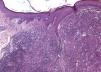

Histopathological examination revealed localized dermal proliferation of xanthomatous macrophages, sometimes multinucleated, interspersed with mixed inflammatory infiltrate and fibroblasts (Figures 4 and 5). These findings, in correlation with clinical examination and dermoscopy, supported the diagnosis of JXG.

JXG is histopathologically characterized by dense pleomorphic histiocytic dermal infiltrates, with a predominance of vacuolated cells at earlier stages and posterior xanthomatous cells. In the later stages, Touton-type multinucleated xanthomatous cells (with provision of nuclei in the periphery of the cytoplasm) are found more easily, which, although characteristic, are non-specific.3,7,10